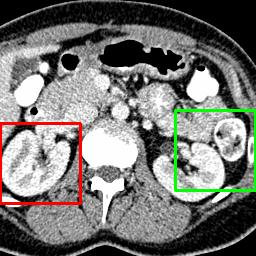

Due to the constraints of the imaging device and high cost in operation time, computer tomography (CT) scans are usually acquired with low intra-slice resolution. Improving the intra-slice resolution is beneficial to the disease diagnosis for both human experts and computer-aided systems. To this end, this paper builds a novel medical slice synthesis to increase the between-slice resolution. Considering that the ground-truth intermediate medical slices are always absent in clinical practice, we introduce the incremental cross-view mutual distillation strategy to accomplish this task in the self-supervised learning manner. Specifically, we model this problem from three different views: slice-wise interpolation from axial view and pixel-wise interpolation from coronal and sagittal views. Under this circumstance, the models learned from different views can distill valuable knowledge to guide the learning processes of each other. We can repeat this process to make the models synthesize intermediate slice data with increasing inter-slice resolution. To demonstrate the effectiveness of the proposed approach, we conduct comprehensive experiments on a large-scale CT dataset. Quantitative and qualitative comparison results show that our method outperforms state-of-the-art algorithms by clear margins.